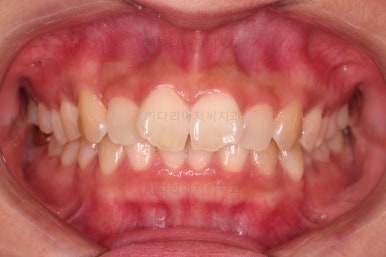

오늘 부산앞니부분교정 키다리아저씨치과에서 소개해 드릴 환자분은 위아래 앞니가 삐뚤어 부분교정으로 개선하고자 하셨던 분입니다.

1. 초진

초진 시 입안의 모습입니다.

어금니 쪽은 약간 삐뚤긴 하지만 꼭 교정해야 할 정도는 아니고, 불편감 없이 비교적 잘 맞물리는 상태였습니다.

다만, 앞니ㅉㄱ이 공간이 부족해서 중간 치아들이 많이 회전되어있는데, 이를 환자분들의 표현에 따르면 "나비치아" 라고 부릅니다.

위아래 중간 앞니가 모두 나비치아처럼 되어있고요.

윗니가 아랫니보다 앞쪽으로 나와 있는 모습에 아래앞니가 윗니쪽으로 깊숙이 올라간 "과개교합" 양상을 보였습니다.